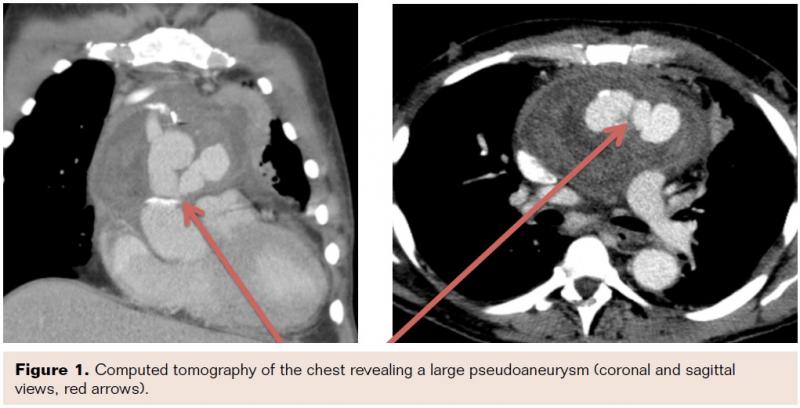

The procedure was performed in the cardiac catheterization laboratory with the patient under conscious sedation. A 6 Fr sheath was placed in the right common femoral artery. Aortic arch angiography was performed with a 6 Fr pigtail catheter and selective angiography confirmed a large ascending aortic PSA (Figure 3).

The patient was given 7,500 units of intravenous heparin and a 5 Fr SIM-1 catheter (Cook Medical) was advanced over a standard .035˝ x 260 cm guidewire into the ascending aorta. The catheter was used to selectively cannulate the ostium of the PSA (Figure 3). A .035˝ x 260 cm straight soft Glidewire (Terumo Medical) was advanced into the PSA (Figure 4). The SIM-1 catheter was exchanged out for a 0.44˝ x 130 mm DAC catheter (Concentric Medical), which was advanced over the wire into the PSA.